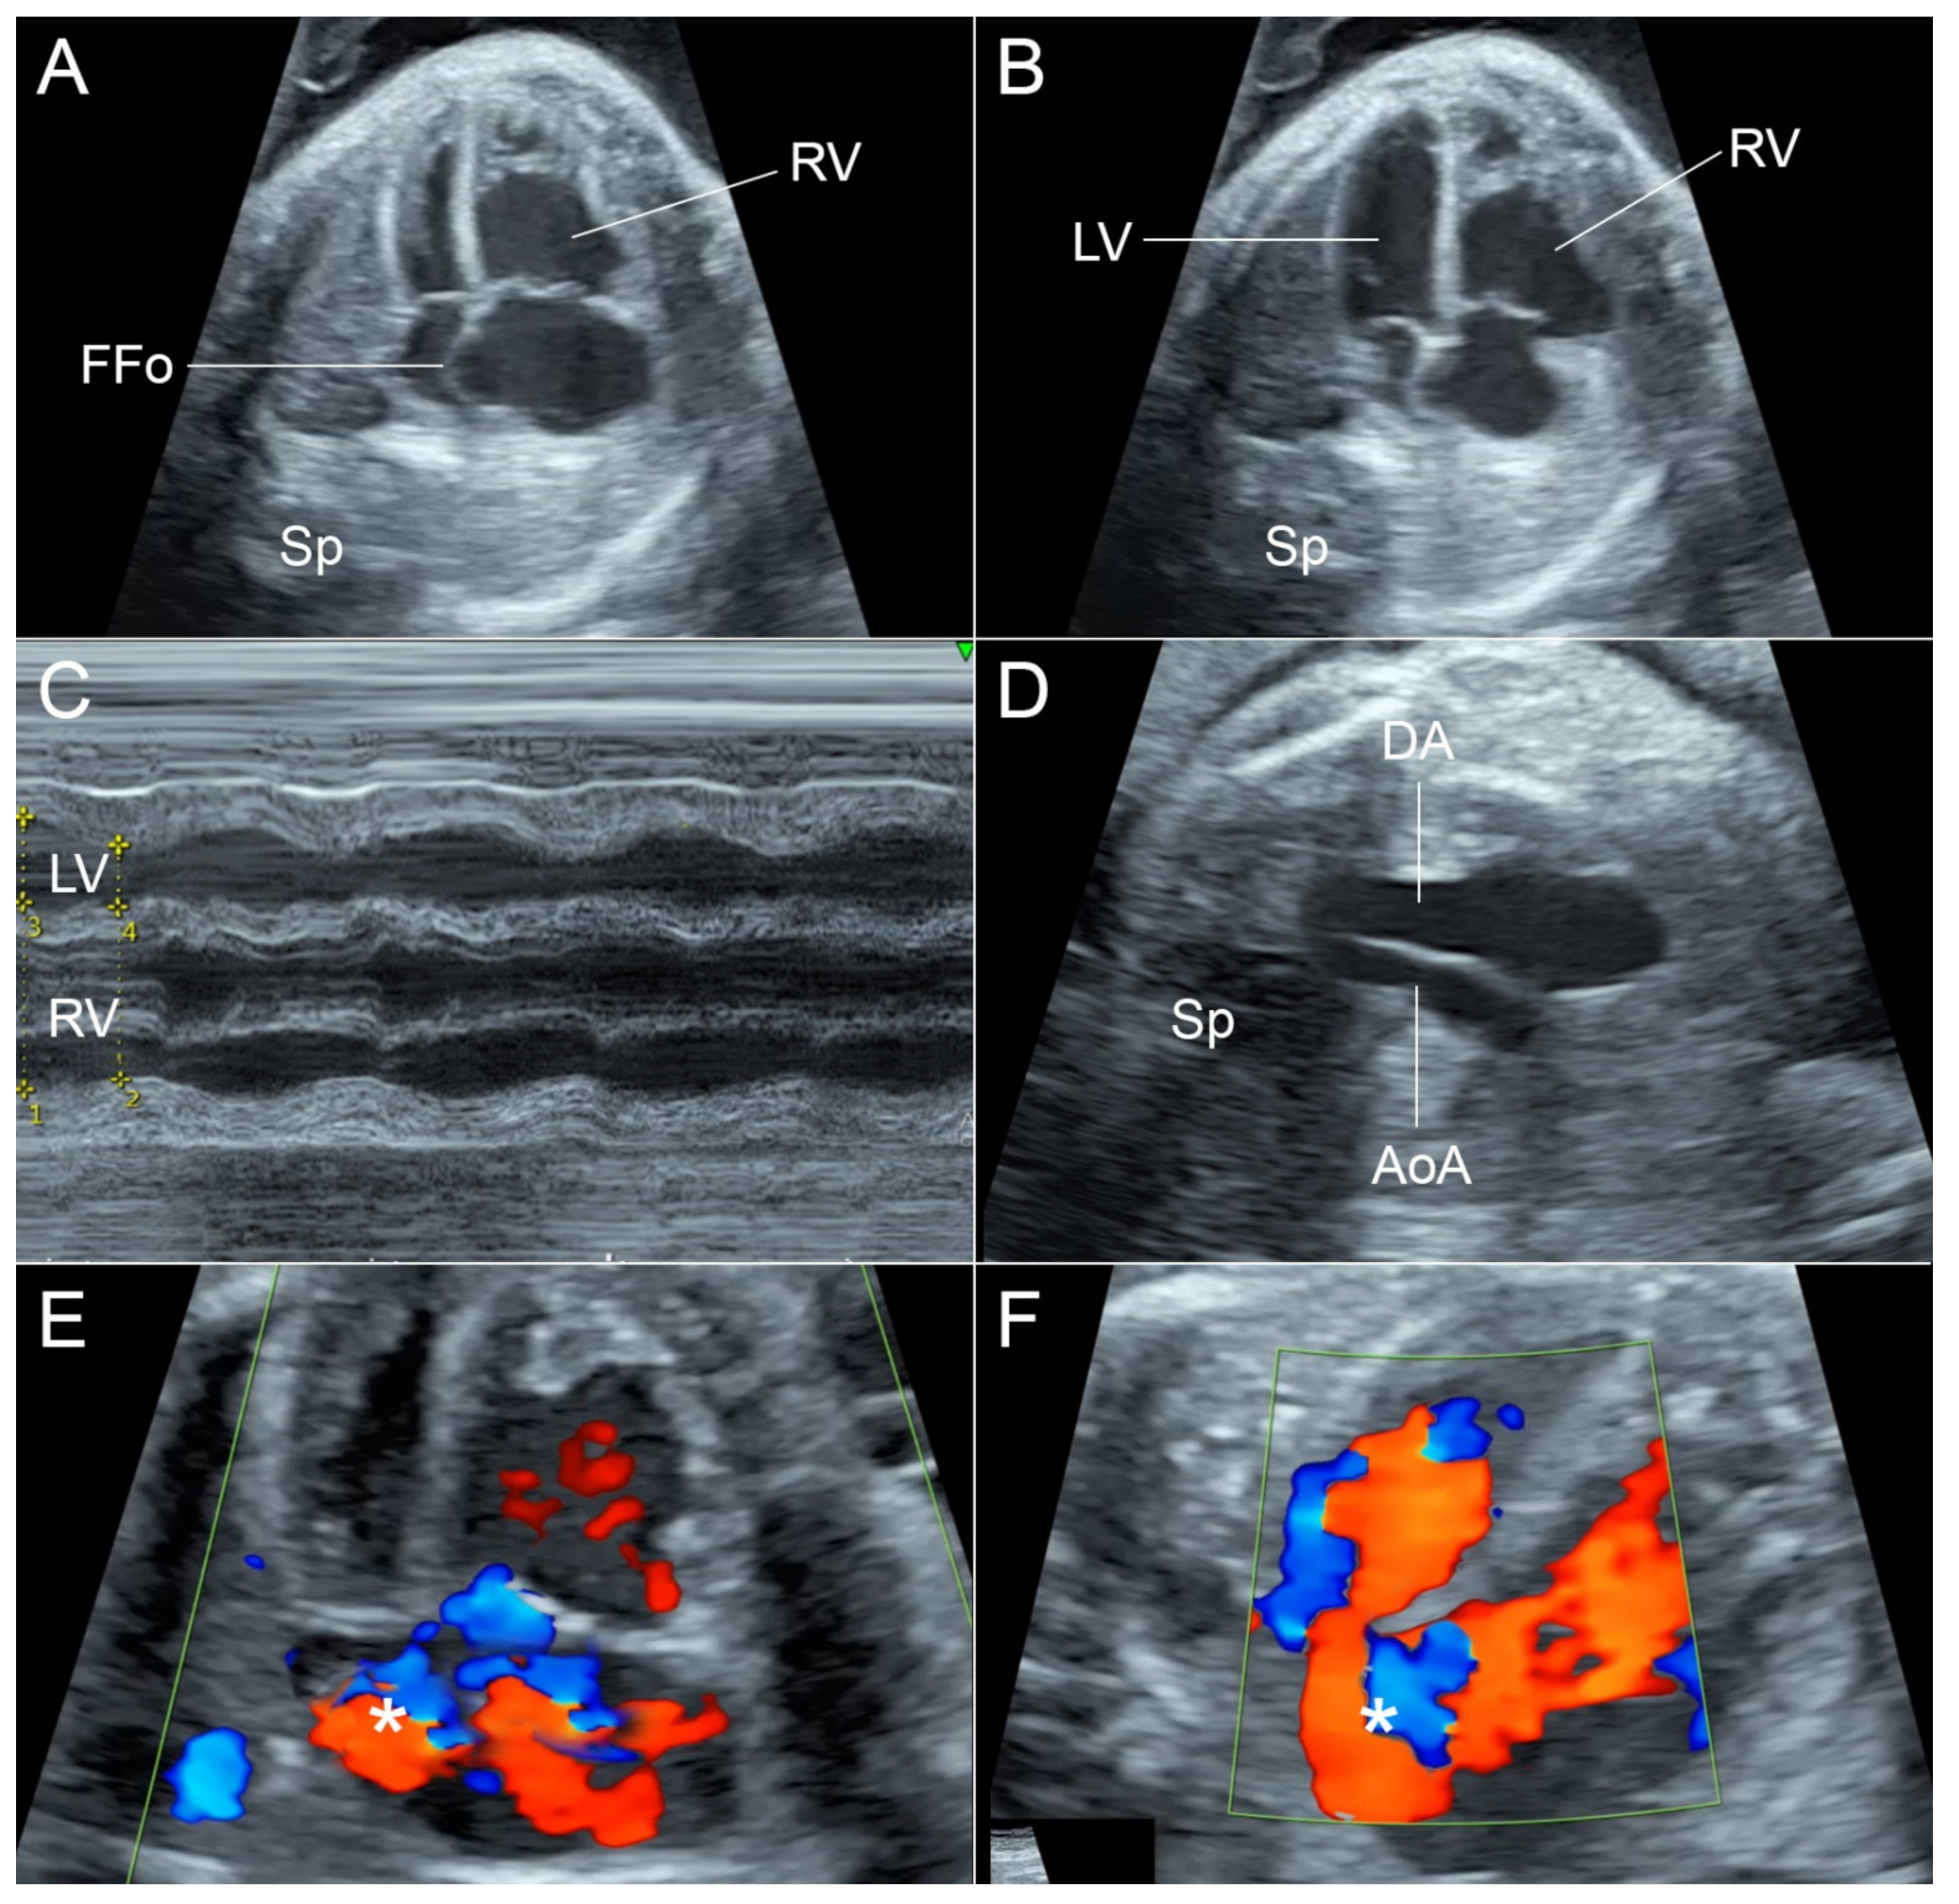

- In anemia, the heart is usually enlarged globally and equally without disproportion [17].